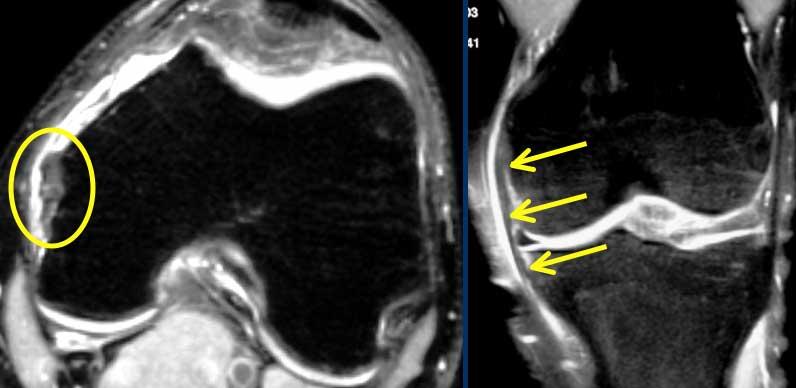

Trên mặt phẳng ngang có dấu hiệu hõm rỗng (mũi tên vàng) ở vị trí lẽ ra ACL phải bám vào lồi cầu. Ở mức thấp hơn (sang phải), ACL đứt đã dính sẹo vào PCL (mũi tên xanh lá).

Trên mặt phẳng ngang cũng phải thấy dây chằng nằm sát bên lồi cầu.

Ở mức thấp hơn, chúng ta thấy ACL đứt bám dính vào dây chằng chéo sau.

Chúng đã dính vào nhau thành sẹo.

Đây là hình ảnh rất thường gặp trong đứt ACL mạn tính.

Sự dính sẹo này tạo ra góc gấp cấp tính của dây chằng.

Mặc dù ACL đã dính vào PCL, nhưng vẫn không đủ vững và cần phải tái tạo.